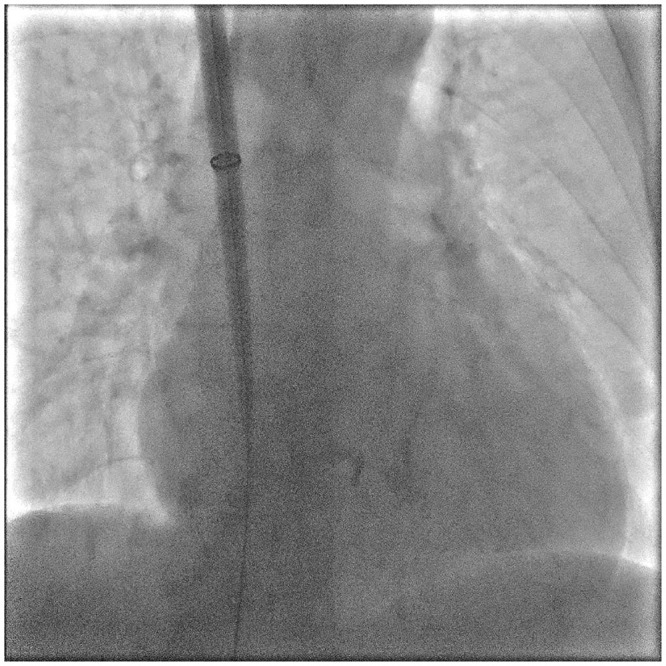

Case presentation: We report the case of a 74-year-old female with sick sinus syndrome, chronic kidney disease, type 2 diabetes, and severe bilateral iliac vein stenosis, who was deemed high-risk for conventional pacemaker implantation. After failed attempts through both femoral veins, the right internal jugular vein (RIJV) was successfully used as an alternative access route for Micra leadless pacemaker implantation. The procedure was performed under ultrasound and fluoroscopic guidance without complications. Post-procedure, the pacing threshold was 0.75 V, sensing was 8.5 mV, and impedance was 760 Ω, all within normal limits.